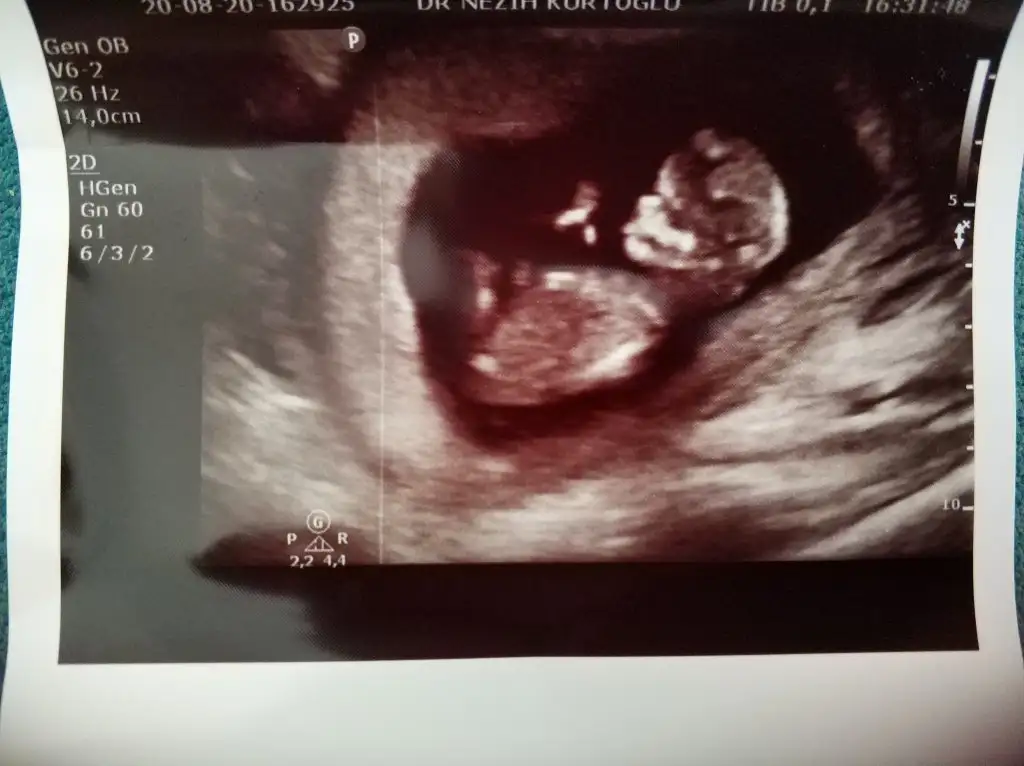

Erkek gibi sanki 13 hafta olursa tekrar paylaşın net değil USG emin olamadimMerhaba 11+6 günlük bebeğim. Bana da tahmin yapabilir misiniz? Eki Görüntüle 2680665

Bana da kız gibi geldi ama hayırlı bakalım. Teşekkür ederim.Erkek gibi sanki 13 hafta olursa tekrar paylaşın net değil USG emin olamadim